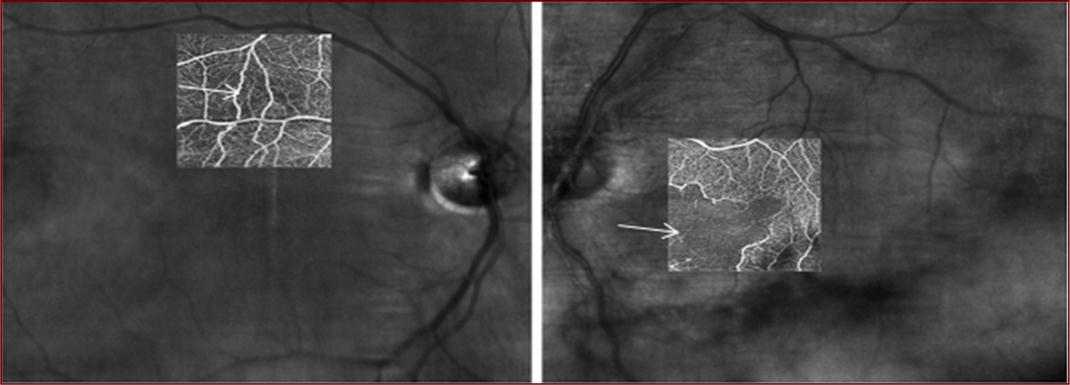

Image 3.Fluorescein angiography two months after first presentation showing mild capillary drop out in the right eye (arrow) and several arterial occlusions in the left eye (arrows).

Fluorescein angiography two months after first presentation showing mild capillary drop out in the right eye (arrow) and several arterial occlusions in the left eye (arrows).